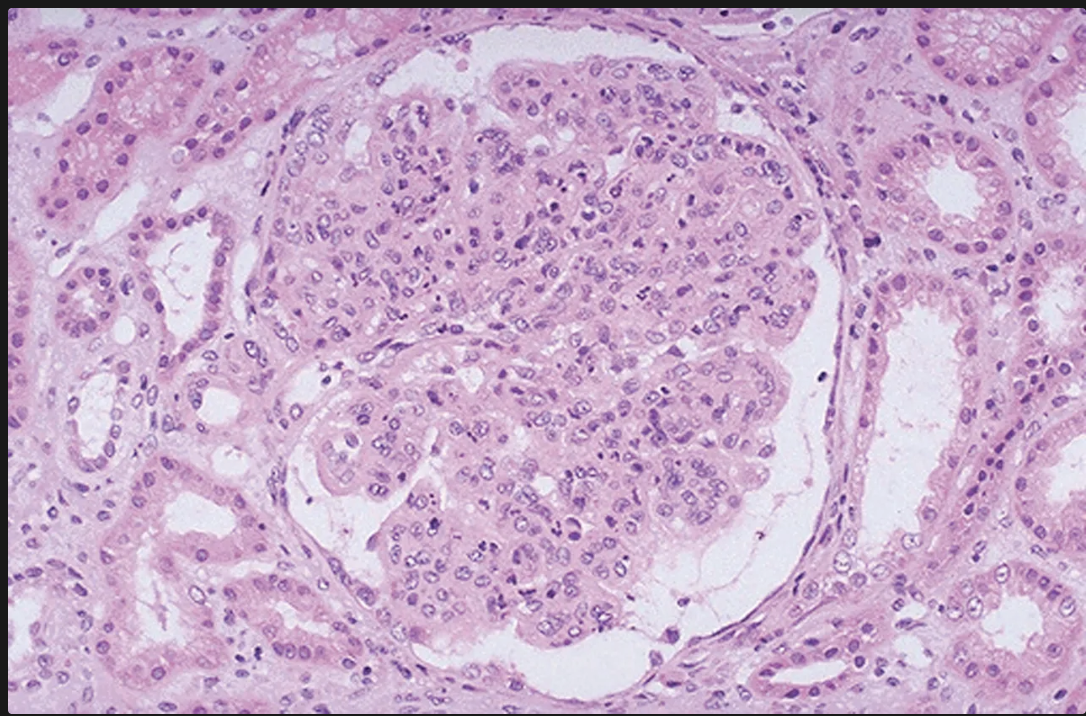

Cómo se ven los glomérulos en la glomerulonefritis infecciosa?

Glomérulos hipercelulares de gran tamaño

Infiltración de leucocitos (es global y difuso osea en tdoso los lóbulos de todos los glomérulos)

Proliferación de células endoteliales y mesangiales

Formación de semilunas